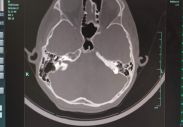

3. 影像学检查 CT,显示双侧前庭导水管扩大。

大前庭CT